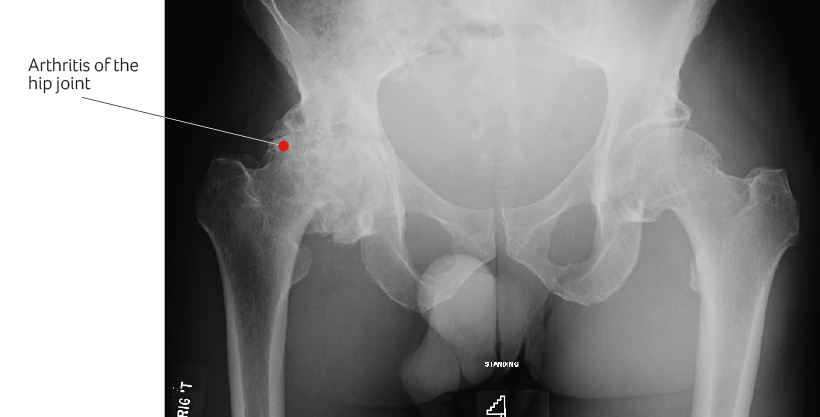

In osteoarthritis, the cartilage over the surface of the joint gradually wears away. This eventually results in exposure of the underlying bone. In addition, the joint in response attempts to heal by forming additional bony spurs known as osteophytes.